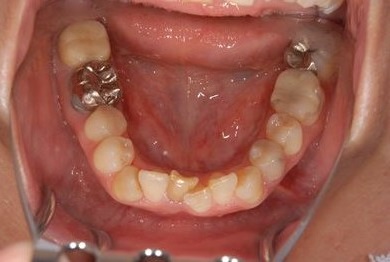

セラミックの症例写真 SHINBI

セラミック治療

| 主訴 | 前歯のさし歯の部分が目立ってしまい、新しくしたい。痛みも少しある。 | ||||||||||||||||||||||||||||||||

| 治療方針 | 保存不能な歯を抜歯し、セラミック治療にて、機能的・審美的回復を行う。 | ||||||||||||||||||||||||||||||||

| 治療内容 | ジルコニアフレームオールセラミッククラウン7本(オールセラミック用土台3本)、ハイブリッドセラミッククラウン1本、ハイブリッドセラミックインレー1本 | ||||||||||||||||||||||||||||||||

| 総治療費 | 1,390,305円 | ||||||||||||||||||||||||||||||||

| 治療期間 | 11ヶ月 |